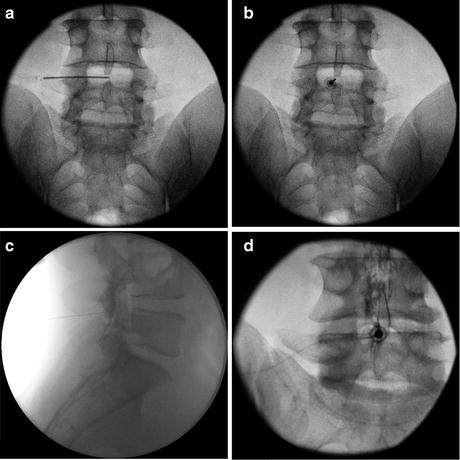

Outside In Technique Clinical Results And Indications With Transforaminal Lumbar Endoscopic Surgery A Retrospective Study On 220 Patients On Applied Radiographic Classification Of Foraminal Spinal Stenosis International Journal Of Spine Surgery